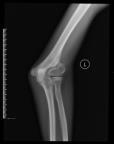

儿童下肢畸形

儿童下肢膝外翻畸形应用“8”字钢板骨骺阻滞术,效果满意